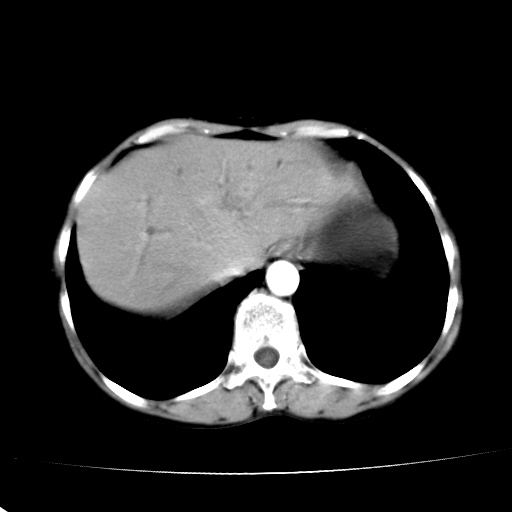

以下是引用jiangjing在2008-6-3 13:36:00的发言:[br]支持 胰头癌------肝内外胆管扩张,胰管扩张,胰头增大,增强见结节状轻度强化影,双管征明显

以下是引用卜一在2008-6-3 14:40:00的发言:[br]支持:胰头癌!(肝内外胆管扩张,胆囊高度扩张,胰管扩张,胰头增大,增强见结节状强化,明显低于胰腺强化密度,并明显见双管征)

以下是引用dyqct在2008-6-3 14:54:00的发言:[br]支持 胰头癌伴肝内外胆管扩张,胰管扩张,胰头增大,增强见结节状轻度强化影,双管征明显。肠系膜上静脉已受侵(已不能手术),建议离子植入治疗吧。